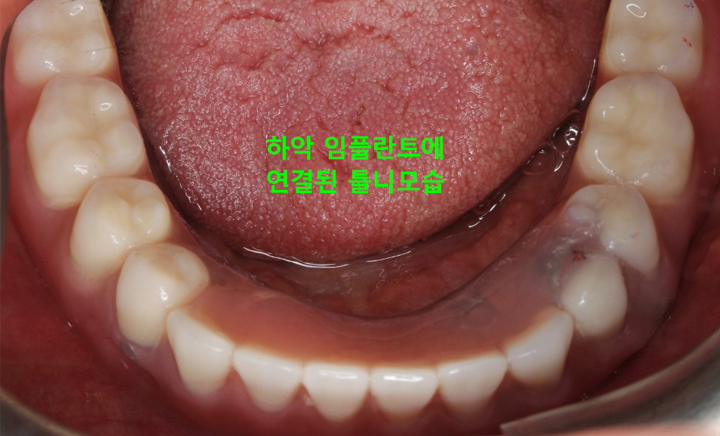

환자분 상태에 따라 임플란트를 2개에서 4개 정도만을 식립하고

그 위에 틀니를 고정시키는 치료 방법

그리고 위턱의 틀니는 입천장이 있어 그나마 고정이 잘되지만 아래턱은 그런 구조물도 없는데다 혀가 자꾸 방해하기 때문에 고정하기가 쉽지 않아 틀니가 움직이는 불편함이 생깁니다. 이러한 틀니의 단점을 보완하고 틀니의 경제성과 임플란트의 기능성을 결합해 만들어진 것이 틀니 임플란트 입니다.

• CASE #2